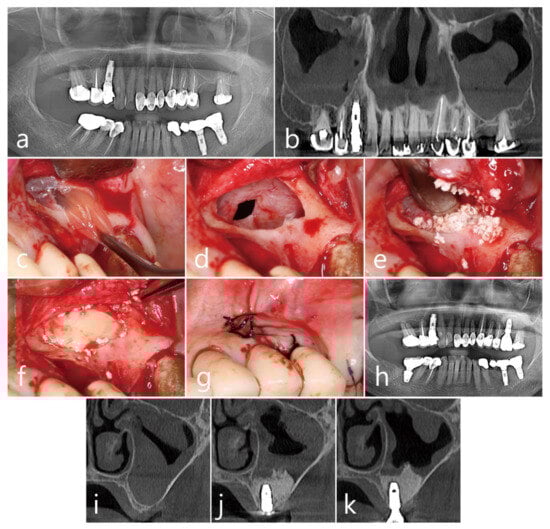

2.4. Case 4